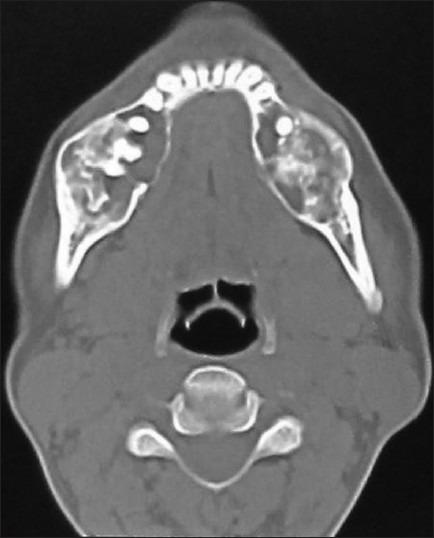

Fibrous dysplasia (FD) has been regarded as a developmental skeletal disorder characterized by replacement of normal bone with benign cellular fibrous connective tissue. It has now become evident that FD is a genetic disease caused by somatic activating mutation of the Gsα subunit of G protein-coupled receptor. Here we report a case of bilateral monostotic FD in a middle-aged female showing a classic histological picture, but radiologically presenting as a mixed radiolucent radiopaque lesion showing nonspecific cystic degeneration.

骨纤维异常增殖症(FD)被认为是一种发育性骨骼疾病,其特征是正常骨被良性细胞性纤维结缔组织所替代。现在已经明确,FD是一种由G蛋白偶联受体的Gsα亚基的体细胞激活突变引起的遗传性疾病。在此,我们报告一例中年女性双侧单发性FD病例,其组织学表现典型,但放射学上表现为混合性透射线不透射线病变,显示非特异性囊性退变。